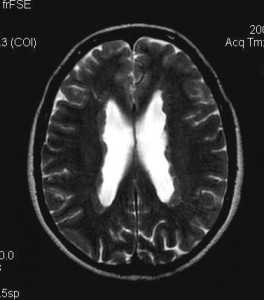

Субэпендимальная гетеротопия серого вещества

Субэпендимальная гетеротопия (перивентрикулярная гетеротопия) - наиболее распространенная форма гетеротопии серого вещества (СВ), характеризующаяся узелками СВ с локализацией непосредственно под эпендимой боковых желудочков. В соответствии с морфологией может быть разделена на:

- унилатеральную фокальную

- билатеральную фокальную

- билатеральную диффузную: волнообразная полоска СВ, окружающая желудочки.

Методом выбора является МРТ, хотя перивентрикулярная гетеротопия видна на КТ и УЗИ (при очень большом размере).

Субэпендимальные узелки СВ обычно гиперэхогенны по сравнению с нормальным белым веществом, а также они могут выступать в просвет желудочков (волнообразный край желудочка).

На КТ субэпендимальная гетеротопия выглядит как некальцифицированный участок ткани, не накапливающий контрастное вещество, по плотности, схожей с нормальным серым веществом, вокруг боковых желудочков.

Постнатальная МРТ

Небольшие узелки серого вещества наблюдаются в эпендимальном слое и искажают контур желудочков. Чаще всего локализация в области треугольника и затылочных рогов. Другие отделы головного мозга выглядят нормальными.

Узелки серого вещества визуализируются на всех последовательностях, в том числе на постконтрастных, где они, подобно нормальному серому веществу, не накапливают контрастное вещество.